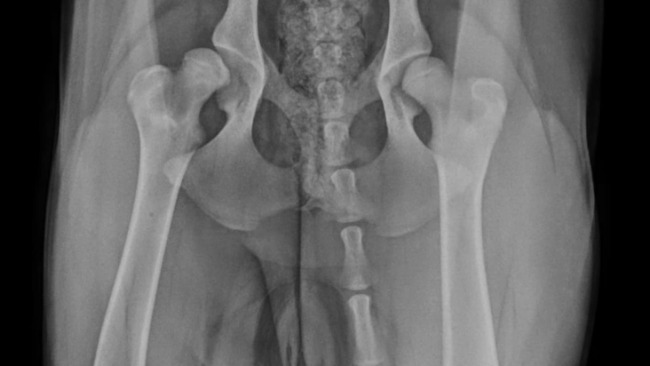

Jestem właścicielem owczarka podhalańskiego 8 miesięcy, ma dysplazję stawów biodrowych,stan bardzo poważny ( zdjęcie z badania i opis badania ortopedy ) rokowania 6 miesięcy do utraty pieska ,a ma dopiero 8 miesięcy, nie jestem w stanie pokryć kosztów leczenia ,(proteza jednego stawu to 5000 euro ).